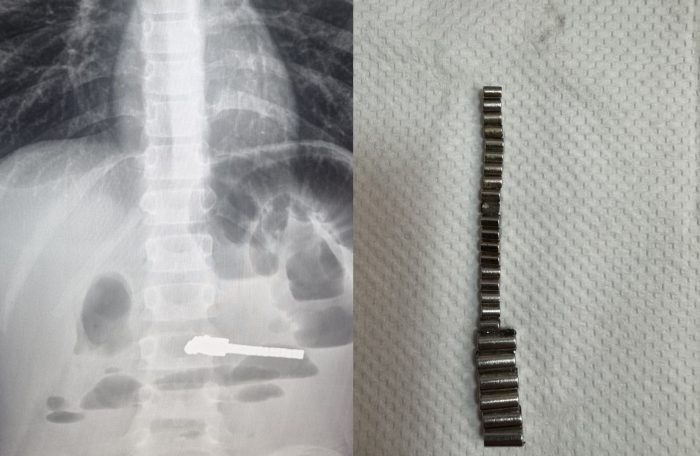

В Новосибирске 25 проглоченных магнитов проделали дыру в желудке ребенка

В Новосибирске ребёнка пришлось экстренно оперировать, чтобы извлечь из него 25 проглоченных магнитов. За то время, что они были внутри, у малыша образовались серьёзные осложнения, вплоть до дыры в желудке и свищей в кишечнике.

Фото ДГКБ №1.

Операция была проведена в экстренной хирургии Детской городской клинической больницы №1. В медучреждении рассказали, что в приемное отделение поступил ребенок с жалобами на постоянную рвоту и сильные боли в животе. Было проведено обследование, в ходе которого рентген «подсветил» посторонние объекты в желудочно-кишечном тракте.

«Обследование выявило множественные рентгенконтрастные предметы в кишечнике и явные признаки кишечной непроходимости. Ребенок был экстренно прооперирован, и в ходе операции было удалено 25 магнитов. К сожалению, длительное нахождение этих предметов в ЖКТ уже привело к серьезным осложнениям: перфорации стенки желудка, тонкой кишки и образованию межкишечного свища», — говорит главврач ДГКБ №1 Евгения Аверкина.

Отмечается, что ежегодно в хирургию детской больницы госпитализируют 3-7 ребят с инородными телами в животе, но случаи с магнитами вызывают особую тревогу. Они притягиваются друг к другу через стенки кишечника, что приводит к непроходимости, некрозу тканей, перфорации (образованию отверстия в стенках желудка или кишечника в результате некроза или сильного давления) и формированию свищей (неестественных сообщений между органами), как и получилось в данном случае.

К счастью, операция прошла успешно, жизни малыша это теперь не угрожает. Медики напоминают, что дети, особенно маленькие, склонны пробовать на вкус любые мелкие предметы, и призывают родителей хранить мелочь подальше. Стоит регулярно проверять игрушки на наличие повреждений и отсутствие деталей, а при появлении у детей болей в животе, рвоты, отказа от еды немедленно обращаться за медицинской помощью. Особенно если есть подозрение, что ребенок всё-таки что-то проглотил.